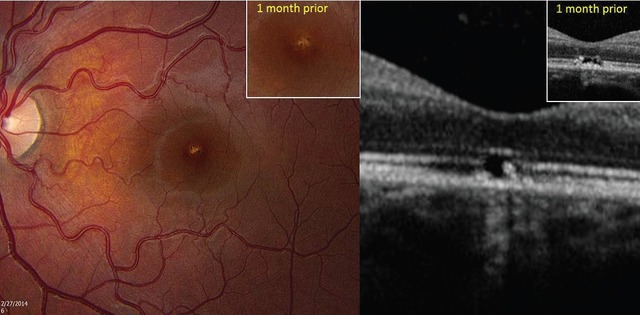

患儿被诊断为左眼激光引起的黄斑病变,并进行随访观察。4 周后,左眼旁中心视力提高到 0.8,左眼中心暗区分辨率有所提高。视网膜检查同样提示黄斑周围 RPE 缺失,OCT 表示 ELM 连续性好转,RPE 相邻的高反射增厚区减少(图 4)。

图 4 随访 1 个月后,左图眼底照片提示左眼 RPE 缺失,右图 OCT 提示 ELM 可见性改善,RPE 上的高反射物质减少。